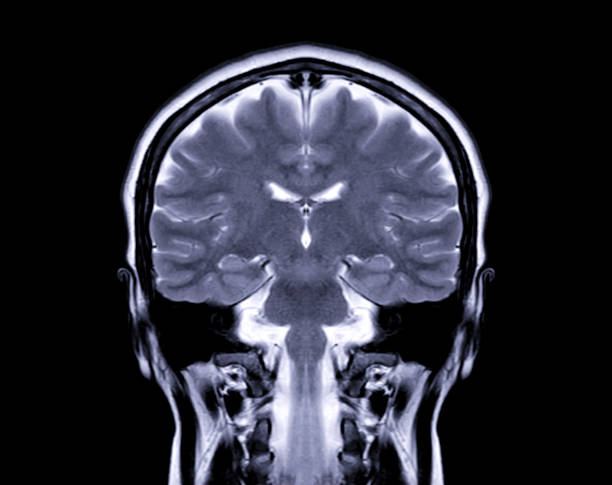

Магнитно-резонансная томография (МРТ) – это метод медицинского образования, который использует магнитные поля и радиоволны для создания детальных изображений внутренних органов и тканей человека. МРТ снимки представляют собой трехмерные данные, содержащие информацию о структуре и состоянии органов. Они широко используются в медицинской диагностике, позволяя врачам обнаруживать и анализировать различные патологии и заболевания.

Магнитно-резонансная томография (МРТ) – это метод медицинской визуализации, который использует магнитное поле и радиоволны для создания детальных изображений органов и тканей вашего тела.

Большинство аппаратов МРТ представляют собой большие магниты в форме кольца или трубки. Когда вы лежите внутри МРТ, магнитное поле временно вызывает отклик молекул воды в вашем теле. Радиоволны заставляют выровненные атомы (чаще всего ядра атомов водорода) генерировать слабые сигналы, которые используются для создания изображений – спиральных или в поперечном сечении (как нарезанный батон хлеба).

Также создаются трехмерные изображения, которые можно просматривать под разными углами.

МРТ головного и спинного мозга

МРТ является наиболее часто используемым методом визуализации головного и спинного мозга. Это помогает диагностировать: